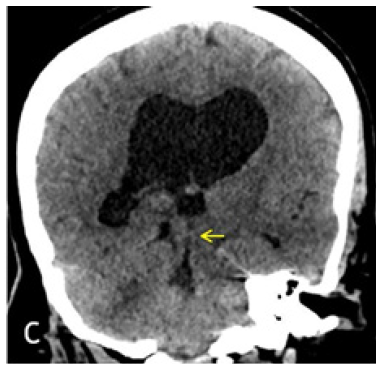

Figure 1C: Coronal reconstruction from Axial 1mm CT slices. Dilated lateral and third ventricles with normal appearing fourth ventricle. Yellow arrow points to the AW/D.

MRI brain was performed in a 3T Siemens Vireo magnet. The additional axial CISS 3D sequence was obtained with isotropic 0.6 x 0.6 x 0.6 voxels taking 7.18 minutes. Sagittal and Coronal reconstructions clearly demonstrated the AW/D Despite the Motion ArtiFact (Figure 2B) (Figure 2C).